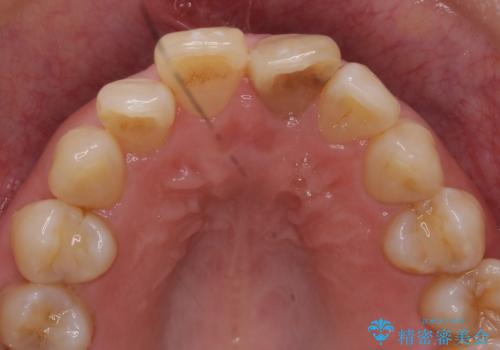

左上の前歯の神経が失活(死んでいた)していたため、神経の治療を行いました。

また、右上の前歯を下げるため、便宜的に神経を取る治療を行いました。

右上1はひっこめた量が大きかったため、反対側の1番と切端をそろえるのに、多少長さは長くなりました。

右上2、左上2の補綴も提案はしましたが、最小限の本数で行っていくことになり、右上2の捻転(歯のねじれ)はそのままとなっております。